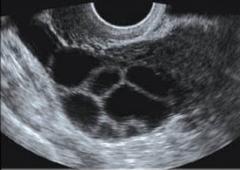

An ultrasound image of stimulated ovary with multiple follicles visible (dark spots)